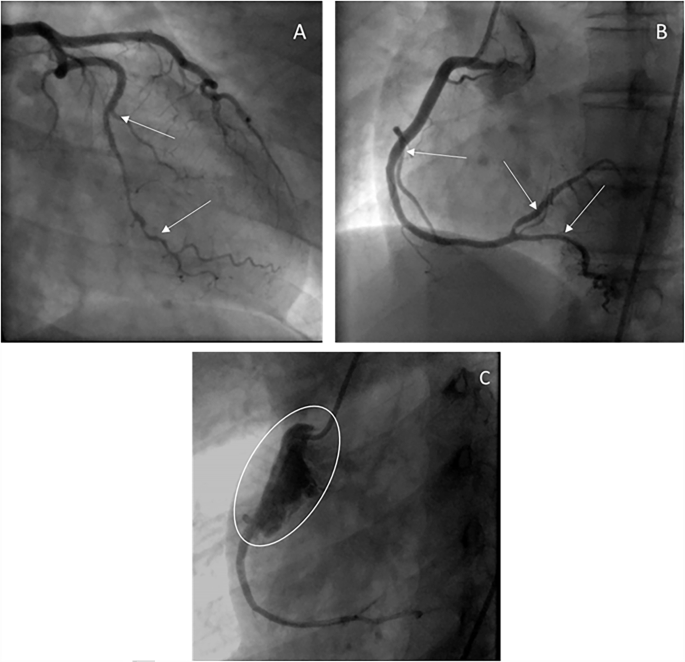

The proportion undergoing intervention was similar in the two groups, as was the complication rate. Three of the SCAD-vEDS cases (cases 1, 6 & 10) underwent stent insertions and two of these cases experienced complications. The two cases where the diagnosis of vEDS was known prior to the SCAD event underwent intervention rather than conservative management. The proportion treated with stenting was very similar to the control group (25% stents in SCAD-vEDS cases versus 26.7% in SCAD-nonvEDS controls). In Case 1, a coronary rupture occurred shortly after catheter intubation of the coronary ostium and extravasation of contrast was evident as was a spiral dissection. After the procedure this patient also developed a right iliac artery dissection (Fig. 1). In Case 10, the RCA was cannulated (femoral artery approach) with initially improved ECG changes but subsequently a catheter-induced dissection in very proximal RCA at catheter tip occurred, which spiralled down RCA leading to a stenosis before bifurcation. The proximal dissection was treated with a stent and distal RCA was also stented just proximal to bifurcation. Three further stents were inserted.

• Multivessel dissection of circumflex (A—white arrows) and right coronary (B—white arrows). • Further angiography was complicated by an extensive iatrogenic dissection/perforation shortly after catheter intubation of the coronary ostium and resulted in a spiral dissection flap contrast extravasation (C). • The right coronary artery was treated with a covered stent. The circumflex was managed conservatively. • Post-procedure, she also developed a right iliac artery dissection.